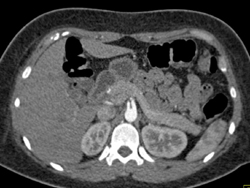

Diagnosis

Normal Coronary Arteries